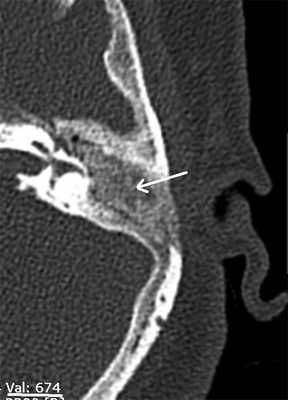

Рис. 1. КТ височных костей пациентки М. а — коронарная проекция: деструктивная полость в пирамиде височной кости, заполненная субстратом неоднородной плотности, капсула лабиринта значительно разрушена на уровне базального и апикального завитков улитки, латерального и верхнего полукружных каналов; б — аксиальная проекция: деструктивная полость с разрушением задней грани пирамиды, передневерхней и нижней поверхности.